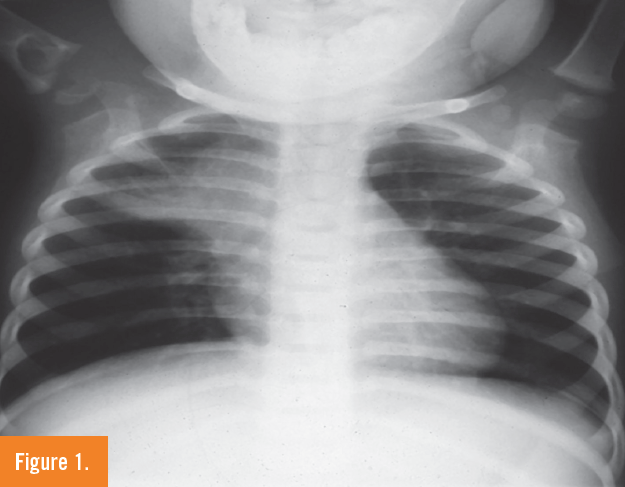

Surasak Puvabanditsin, MD; Imteyaz Khan, MD; Syed-Saif Abbas Rizvi, MBBS; Imran Malik, MD; Barry Weinberger, MD; Thomas Hegyi, MD

An infant was born via cesarean delivery to a 29-year-old, gravida 3, para 2 mother at 31 weeks’ gestation. The pregnancy had been complicated by preterm labor and preeclampsia.